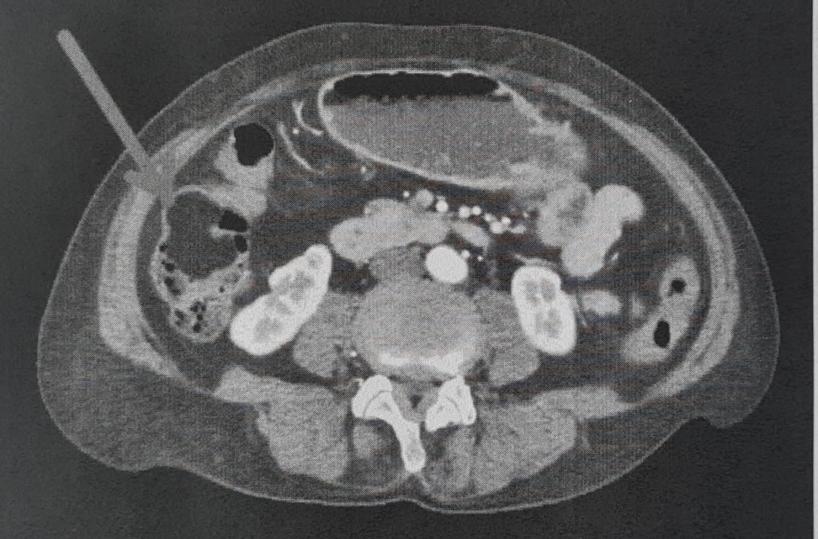

La paziente pensava di essere afflitta da un banale quanto fastidioso mal di pancia. Gli approfondimenti diagnostici eseguiti, infatti, hanno chiarito un quadro clinico complesso e rivelato, grazie ad una Tac all'addome, la subocclusione intestinale dovuta alla presenza di una massa tumorale di oltre 6 centimetri di diametro, sviluppatasi all’interno della parete del colon destro, confermata da una successiva colonscopia. Dopo il completamento delle indagini strumentali e un’attenta valutazione anestesiologica, la paziente è stata sottoposta ad Emicolectomia destra laparoscopica, un intervento chirurgico mini-invasivo per la rimozione del tumore annidato nella parte destra del colon. Il decorso postoperatorio, con dimissione dopo dieci giorni, è stato seguito in stretta collaborazione con il team di cardiologi e internisti del presidio.

"La diagnosi istologica, effettuata presso l’Istituto Oncologico di Bari, è stata di “Lipoma sottomucoso maturo” che, seppur benigno, rappresenta una evenienza non comune", spiega Cianci. "Questi tumori hanno una prevalenza tra lo 0.035% e il 4.4% di tutte le neoplasie benigne non epiteliali del tratto gastrointestinale e, in genere, non causano sintomi se non di grandi dimensioni come nel nostro caso. L’approccio laparoscopico ha sicuramente ridotto i tempi di ripresa, le complicanze postoperatorie e nel complesso la degenza ospedaliera». I numeri della Chirurgia, del resto, confermano la crescita di attività sia in volume sia in qualità dell’assistenza sanitaria. Dal 1° gennaio 2025, infatti, nell’Unità operativa di Chirurgia Generale dell’Ospedale Umberto I di Corato, sono stati effettuati 418 interventi chirurgici, di cui 102 in urgenza e 316 in elezione. Gli interventi con approccio mini-invasivo laparoscopico, con tecniche chirurgiche che utilizzano piccole incisioni per ridurre il trauma, il dolore, il sanguinamento e i tempi di recupero - conclude - sono stati complessivamente 129, il 30,9 per cento del totale".